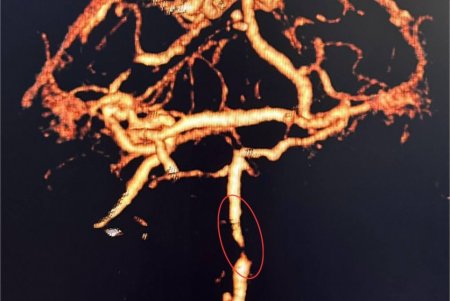

Як розповів завідувач рентгенендоваскулярного блока лікарні Олександр Скрипка, це був один з найскладніших випадків - ураження стовбурової частини мозку. Базилярна артерія була майже повністю закрита атеросклеротичною бляшкою. Такі інсульти належать до найбільш небезпечних, а за відсутності термінової допомоги навіть шанси на виживання мінімальні.

Фахівці прийняли рішення оперувати та провести ангіопластику артерії. Кластерна лікарня №10 має досвід такої методики лікування в кардіології при атеросклерозі коронарних судин, але застосування її для мозкових судин - це інноваційна технологія в масштабах України.

Операція тривала близько 60 хвилин. Звужену артерію розширили за допомогою спеціального балона, а потім застосували балон з лікарським покриттям.